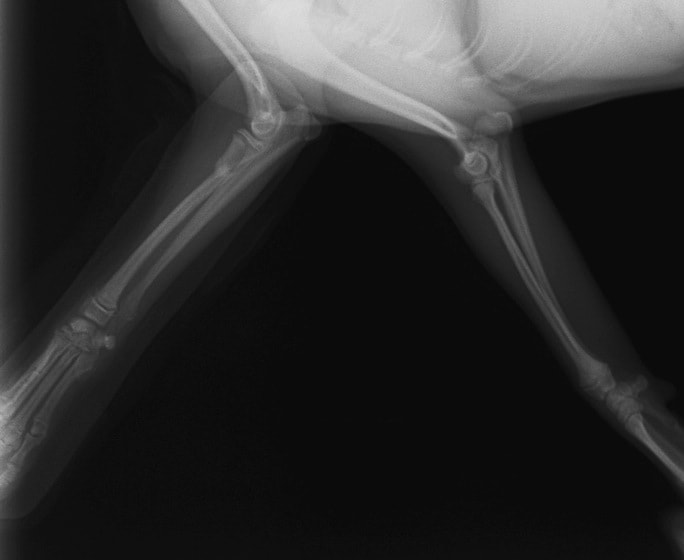

ペルシャ猫 11ヶ月齢 雄

他院にて左大腿骨遠位の成長板骨折(salter-harrisⅠ型)が認められており、治療相談を目的として来院。当院にて、キルシュナーワイヤーを用いたピンニングにより骨折部位の整復を行いました。術後の経過は良好で、現在も経過観察中です。

術前レントゲン